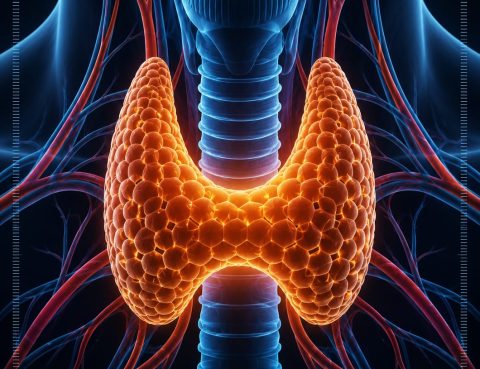

🦋 العناية بالغدة الدرقية تبدأ بالتشخيص الصحيحمع المرشدي للسياحة العلاجية 🤍 اضطرابات الغدة الدرقية قد تؤثر على نشاط الجسم بالكامل، وتسبب أعراضًا مثل التعب المستمر، زيادة أو فقدان الوزن، تساقط الشعر، واضطرابات الهرمونات. اليوم أصبحت علاجات الغدة أكثر دقة وفعالية بفضل التقنيات الطبية الحديثة والتشخيص المبكر ✨ تشمل أمراض الغدة الدرقية:• فرط نشاط الغدة• خمول…